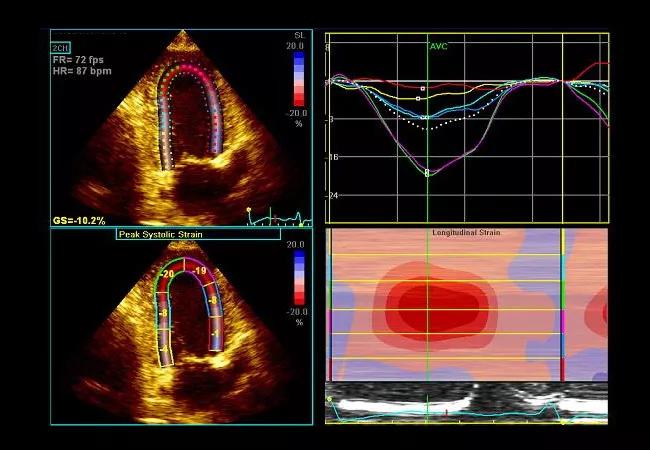

An additional session is focused on special topics including diastolic dysfunction, strain imaging, echo’s role in cardio-oncology and contrast utilization in echocardiography. Optional workshops are offered the first day of the course on the following:

• How to employ strain and 3D volumes/ejection fraction in clinical practice